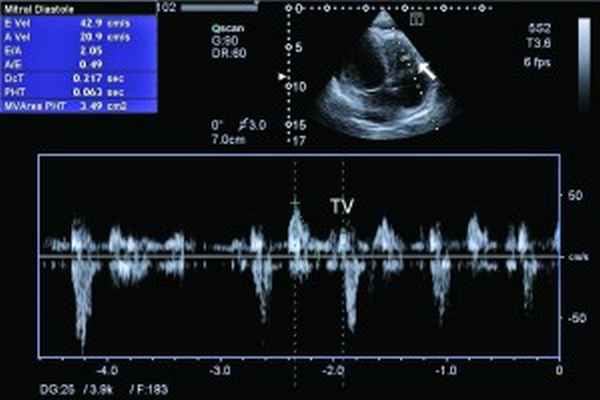

При рентгенологическом обследовании органов грудной клетки обнаруживают кардиомегалию и признаки венозного застоя в легких. Изменения ЭКГ не специфичны. Частые находки – нарушения ритма сердца, особенно фибрилляция предсердий (ФП). В диагностике заболевания основную роль играет эхокардиография (ЭхоКГ), позволяющая обнаружить локальное (реже – диффузное) утолщение верхушки одного или обоих желудочков с вовлечением в патологический процесс хорд, умеренную митральную или трикуспидальную регургитацию, пристеночные, особенно верхушечный, крупные тромбы. Показательным является «рестриктивный тип» ремоделирования сердца и внутрисердечной гемодинамики – очевидное преобладание объема предсердий над объемами желудочков. Систолическая функция, как правило, сохранена, но диагностируется диастолическая дисфункция – рестриктивный тип трансмитрального/транстрикуспидального кровотока. Наиболее информативными методами исследования на сегодняшний день являются магнитно-резонансная томография (МРТ) и мультиспектральная компьютерная томография с контрастированием 13. В литературе описан случай динамического наблюдения за развитием эндокардита Леффлера с серией одновременно производимой позитронно-эмиссионной томографии и контрастированной МРТ с выделением стадий: бессимптомной, острой некротической, симптомной тромботической и фибротической [13]. Выполнение эндомиокардиальной биопсии миокарда правого (ПЖ) или левого (ЛЖ) желудочка позволяет подтвердить или опровергнуть диагноз эндокардита Леффлера.

Рис. 5. Рестриктивный транстрикуспидальный кровоток (допплер)